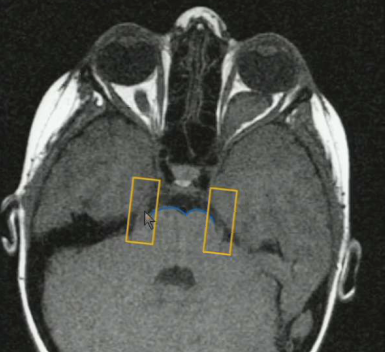

What structures are indicated below?

1) Opthalmic artery branching from carotid and going through the optic canal 2) Basilar artery

What nerve is coming off in the orange boxes? What is the pathology in this patient?

Trigeminal nerve. Note the cleavage of the brainstem (blue), this tells you that you are high up in the pons CN V comes off 1st in the pons. Note the patient has a big left optic nerve glioma.